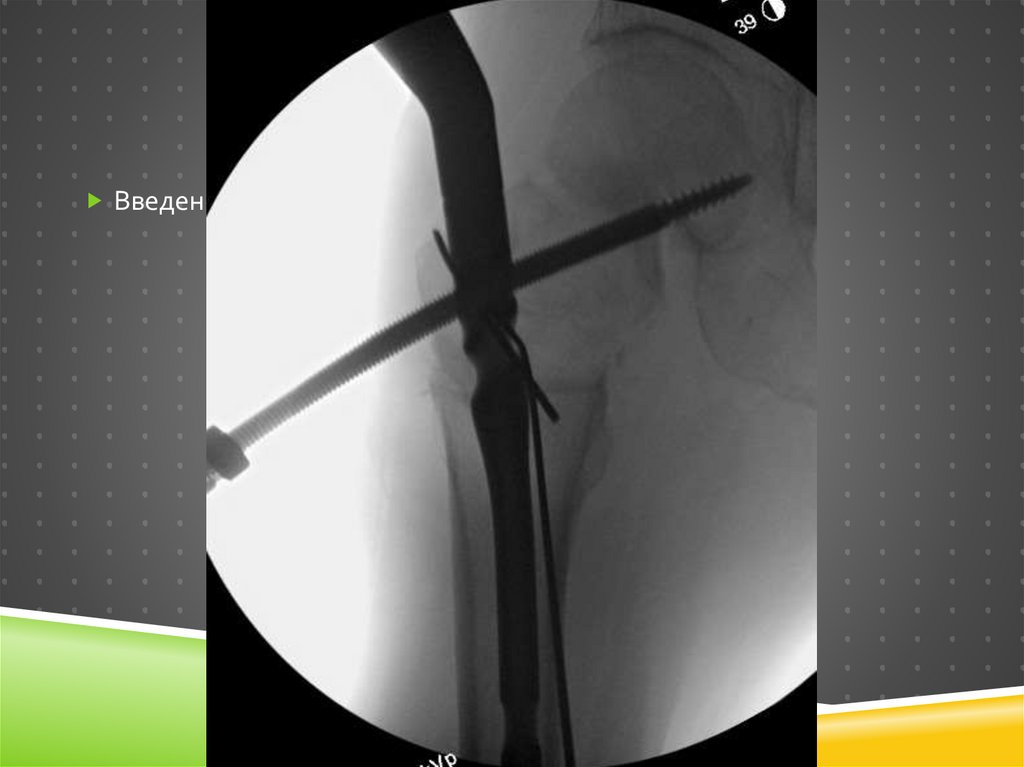

9. Intra-op

INTRA-OP

1

9